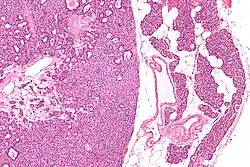

Micrographs